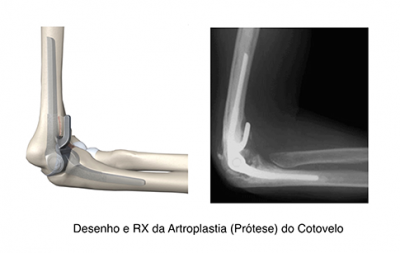

FIGURA 17